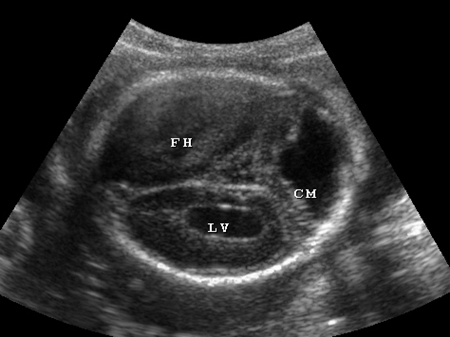

四维彩超侧脑室正常值是多少?孕期准妈妈可以通过四维彩超测量胎儿的侧脑室宽度,那么,四维彩超侧脑室正常值是多少呢?

胎儿侧脑室宽度正常值应该在10mm以下,若超过10mm,被称为侧脑室增宽,是因为脑脊液过多积聚与脑室系统内,使脑室系统扩张所致。通常,侧脑室宽度越宽程度越重,对胎儿的影响越大。若侧脑室宽度超过15mm,被称为脑积水。